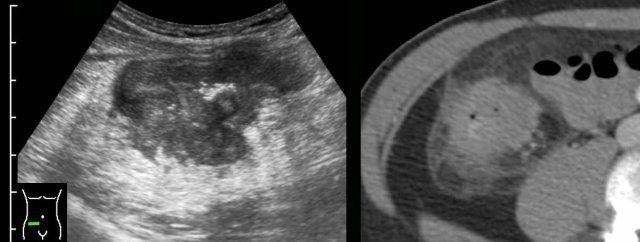

This 18-year old man was admitted with acute appendicitis-like symptoms and immediate CT was performed.

CT revealed evident ileal bowel wall thickening and a normal appendix (not shown here).

Subsequent US showed the typical characteristic transmural hypoechoic changes in the hyperechoic submucosa confirming Crohn’s ileitis.

Note the superior image resolution of US compared to CT.